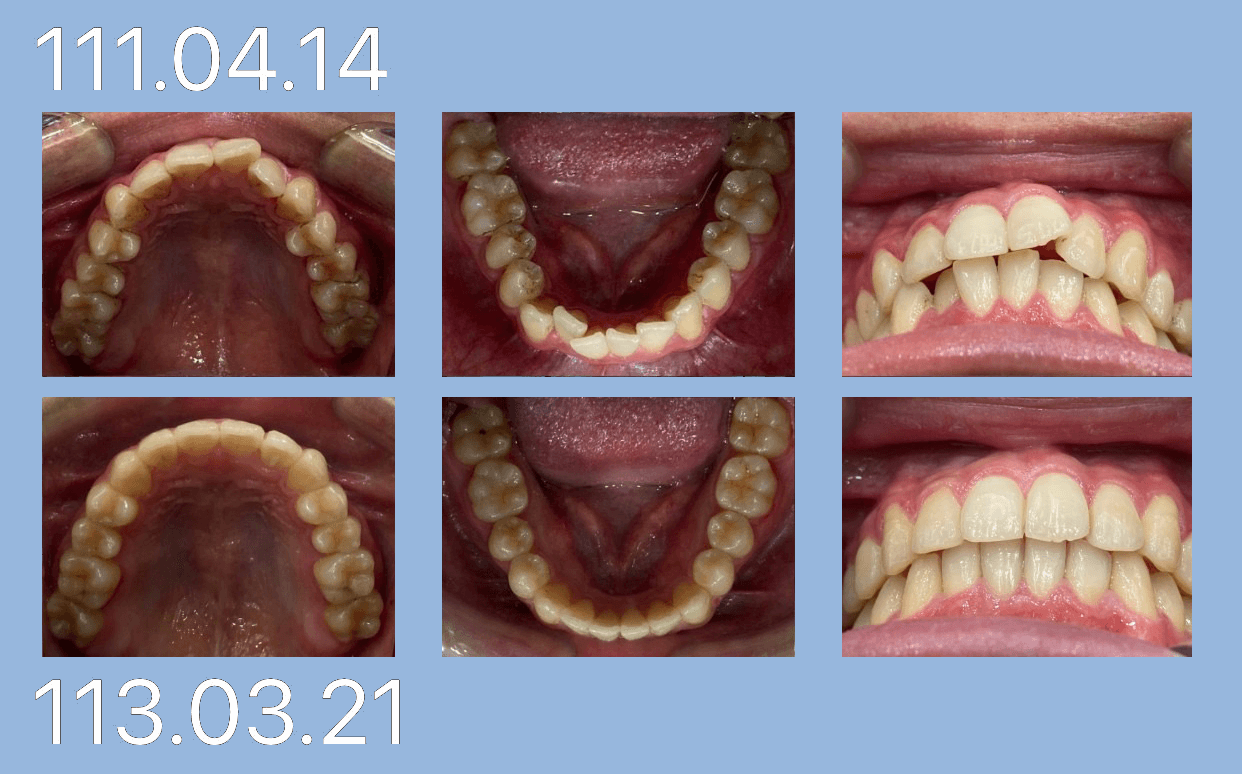

潘小姐 (24歲) 暴牙 第一套矯正結束

狀態:沒拔牙